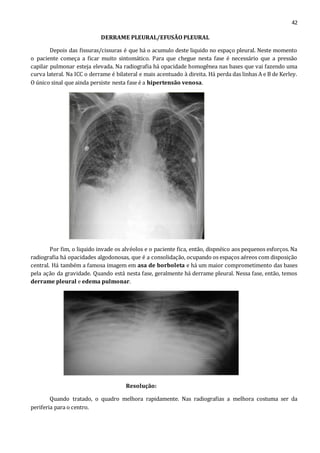

Antes do derrame pleural, esse liquido extravasado vai paras as fissuras. Nessa fase o paciente

está a ponto de descompensar. Na radiografia do perfil a grande cissura é melhor vista do que na padrão

PA. Já a pequena cissura com liquido acumulado é melhor visto na radiografia do tipo PA. O liquido

acumulado nesta cissura pode conferir a ela aspecto ovalado, lembrando um nódulo pulmonar. Se tratado

com diuréticos eles desaparecem, sendo assim chamados de pseudo-tumor.

Depois das fissuras/cissuras é que há o acumulo deste liquido no espaço pleural. Neste momento

o paciente começa a ficar muito sintomático. Para que chegue nesta fase é necessário que a pressão

capilar pulmonar esteja elevada. Na radiografia há opacidade homogênea nas bases que vai fazendo uma

curva lateral. Na ICC o derrame é bilateral e mais acentuado à direita. Há perda das linhas A e B de Kerley.

O único sinal que ainda persiste nesta fase é a hipertensão venosa.

Por fim, o liquido invade os alvéolos e o paciente fica, então, dispnéico aos pequenos esforços. Na

radiografia há opacidades algodonosas, que é a consolidação, ocupando os espaços aéreos com disposição

central. Há também a famosa imagem em asa de borboleta e há um maior comprometimento das bases

pela ação da gravidade. Quando está nesta fase, geralmente há derrame pleural. Nessa fase, então, temos

derrame pleural e edema pulmonar.

Resolução:

Quando tratado, o quadro melhora rapidamente. Nas radiografias a melhora costuma ser da

periferia para o centro.